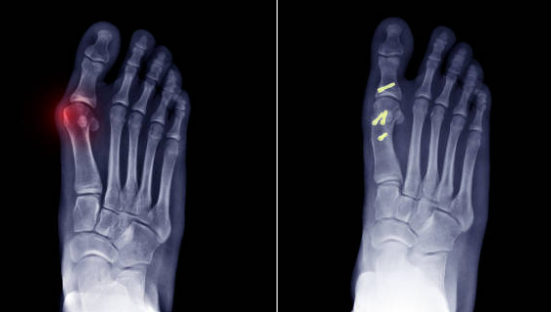

Hallux Valgus

L'Hallux Valgus (ou oignon du gros orteil) est une déformation évolutive du gros orteil

La déformation du gros orteil et l'apparition d'une bosse est caractéristique dans l'Hallux Valgus

Une radiographie du pied est nécéssaire pour confirmer le diagnostic et programmer l'intervention